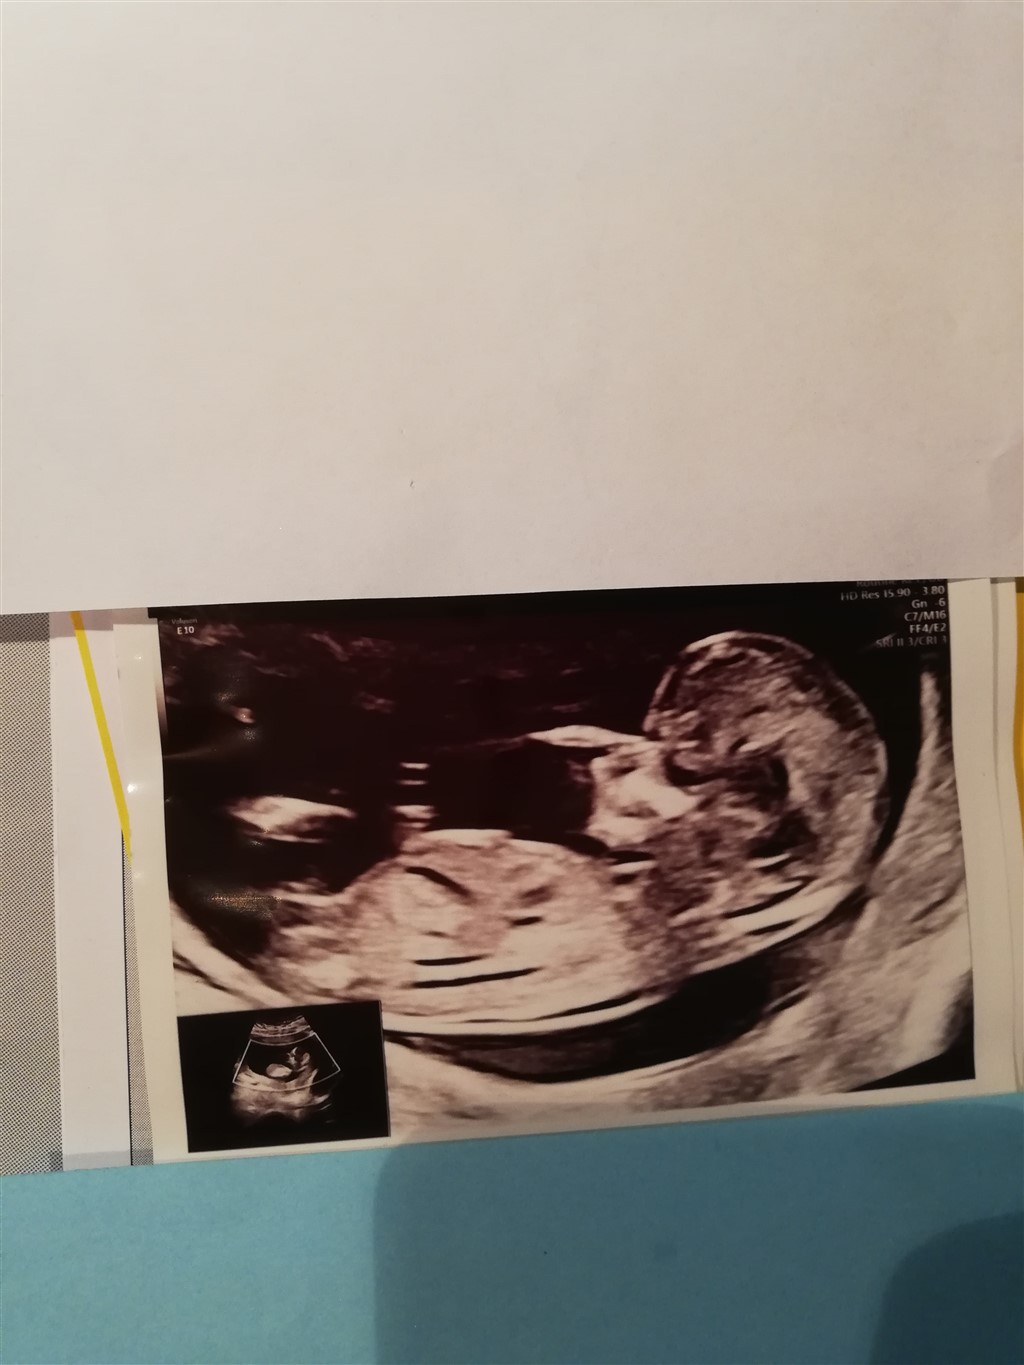

Dreng eller pige? ❤️

Tydelig dreng

Det er svært at forklare på skrift synes jeg. Men prøv og søg på nub Theory på google.